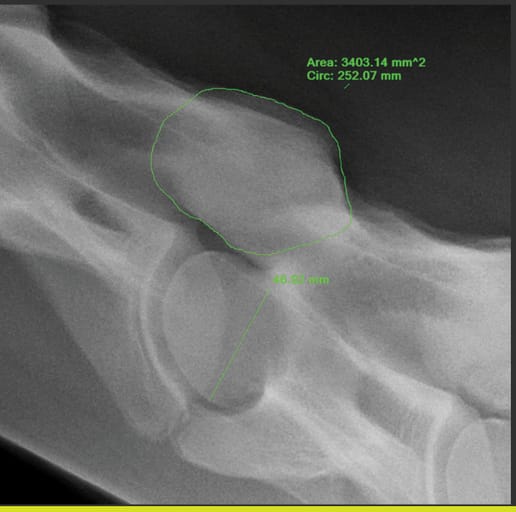

Measurement of articular process joint area and vertebral body height to create APJ area ratio.